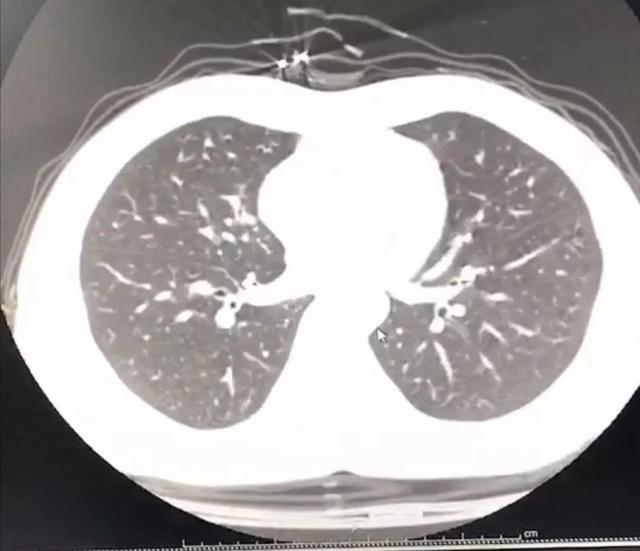

早上醒过来睁开眼第一件事情就是量体温,38.6℃。起床的时候感觉有点轻微的气急,本来稍放松的心情又紧绷了,起来打电话给呼吸科老师,她建议我还是去查一个肺部 CT 更放心一些。

于是拖着沉重的步伐,我又从家里出发去医院做胸部 CT 。幸运的是肺部还没有出现病毒性肺炎的特征性影像学表现,说明就算是新型冠状病毒感染,目前还属于轻型,没有实质性地累及肺组织。

问美胶囊效果怎么样,问美胶囊销售热线(疑似感染新型肺炎)

图片来源:作者提供

即便如此,考虑到父母年纪偏大了,具有高度被感染风险,单纯的房间隔离很难杜绝被感染的风险,所以我从现在的租住屋搬到了自己的房子,一个人隔离起来。